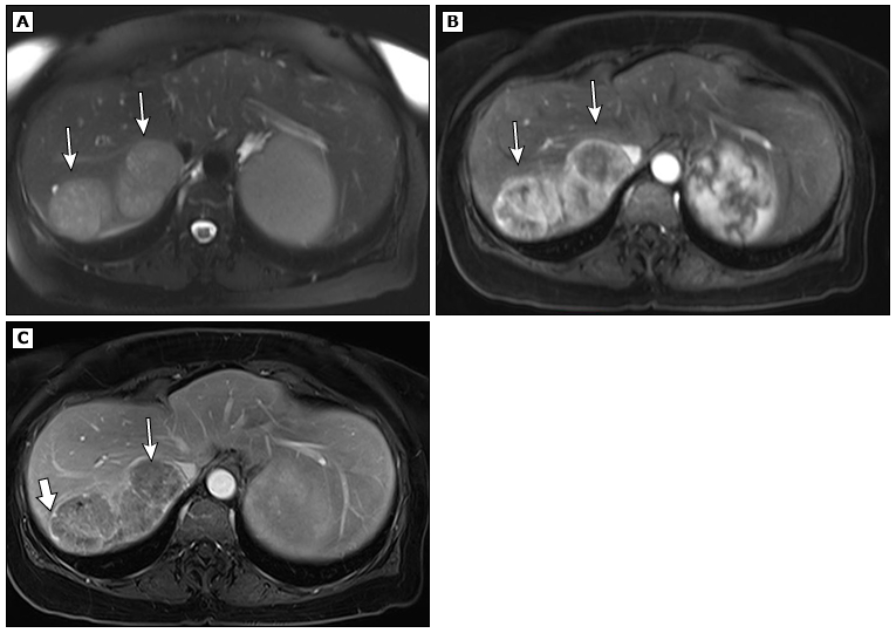

МРТ-снимки гепатоцеллюлярного рака